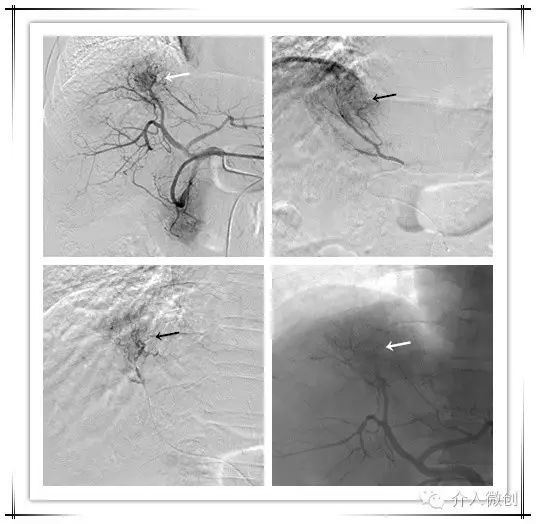

针对新情况,为该患者制定治疗计划:肝动脉化疗栓塞术+射频消融术控制肝内新发瘤灶,并联合碘125放射性粒子植入控制门脉右支癌栓。

DSA造影显示右肝膈顶可见新发病灶肿瘤染色